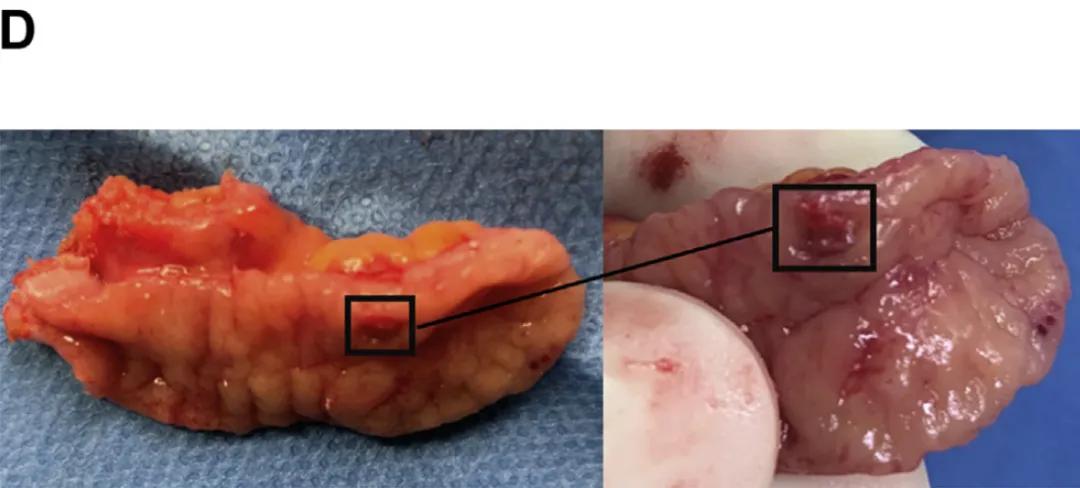

医生推测血液来自阑尾。腹部增强CT扫描(图B)显示阑尾呈高密度改变,其他部位无阳性发现。